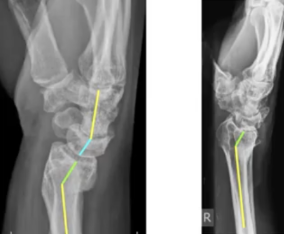

4. Distal Radius Malunion – Simplified for Residents By Dr. Shailesh Pai

Distal Radius Malunion can change the entire biomechanics of the wrist—and this session breaks it down beautifully.

Covers:

• Radiographic parameters

• Types & classifications

• Functional implications

• Management principles every resident must know

A must-watch for OPD, trauma postings, and exam preparation.